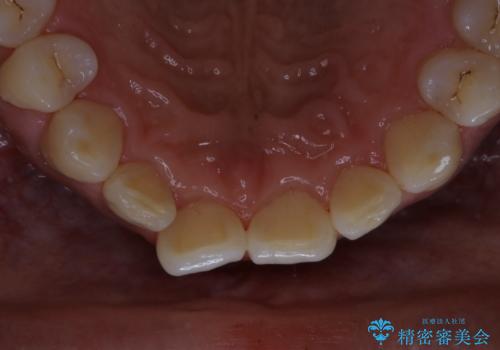

PMTC60分コースを行いました。

PMTC(保険外治療)は、毎日の歯磨きで落としきれない汚れや、コーヒ、紅茶・タバコのヤニなどの着色も除去します。目には見えない歯と歯の間・歯肉の境目・インビザライン中はアタッチメント周囲などに残っているプラーク(歯垢)もしっかり取り除きます。PMTCでは専門的な機械や材料を使用して、徹底的に汚れを除去するため、虫歯・歯周病・口臭予防などにつながります。

またPMTCを行うことで、ご自身本来の歯の色になり自然な明るさになります。